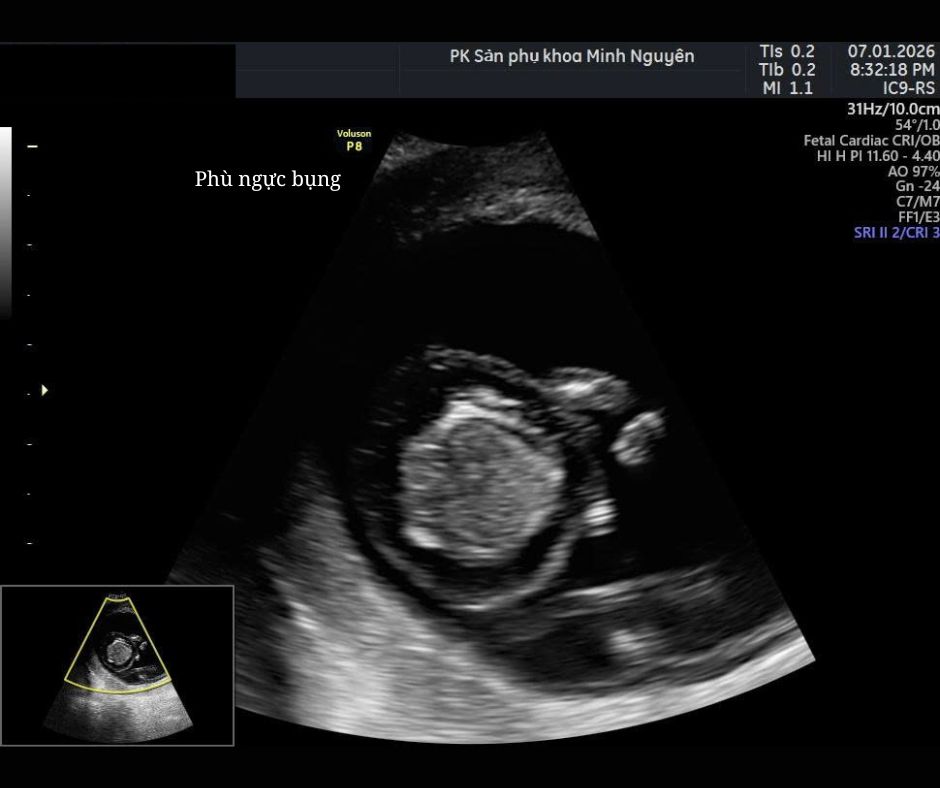

Dấu hiệu phù thai trên siêu âm

Siêu âm là công cụ chính để phát hiện phù thai. Bác sĩ có thể ghi nhận:

- Cổ trướng: dịch trong ổ bụng thai

- Tràn dịch màng phổi: dịch quanh phổi

- Tràn dịch màng tim: lớp dịch quanh tim dày bất thường

- Phù da: lớp da dày, sưng toàn thân

- Bánh nhau dày

- Nước ối nhiều

Chẩn đoán phù thai khi có từ hai dấu hiệu trở lên.